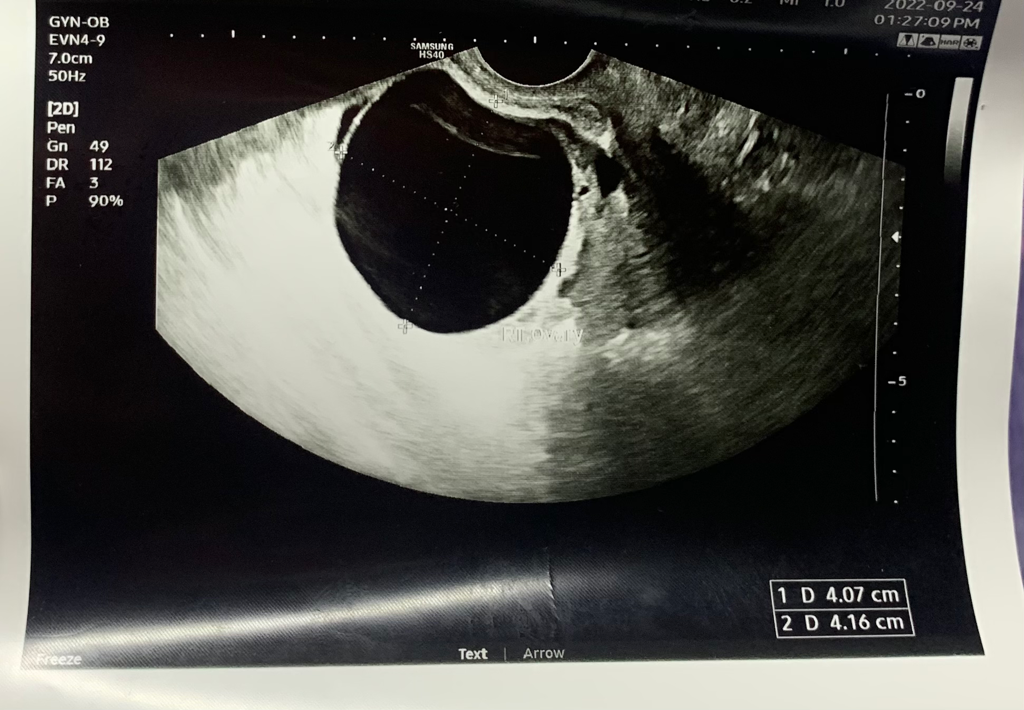

난소 물혹(낭종) 4센티 위험한 건가요? (증상있음)

안녕하세요 21살 대학생입니다. 한달 전에 자궁경부암 검사를 하고 염증 소견이 있다는 말에 바이러스와 세균 검사를 했습니다. 가드넬라 질염과 hpv 저위험군 30이 있다는 말과 초음파도 해보자는 말에 해봤는데 물혹이 큰게 있다고 합니다 어릴 때부터 소변을 자주 봤고 위장도 딱히 좋은 편은 아닙니다. 배란일이나 생리 전에 빈뇨와 아랫배 뻐근? 불편한 느낌이 있었습니다 그런데 최근에 생리 10일 전인데도 빈뇨가 심하고 아랫배 누르면 아프고 누르지 않아도 콕콕 쑤시는 느낌이 들었어요 그런데 딱 물혹이 있다고 하니까 .. 이게 난소암 일 가능성도 있나요? 사진도 꼭 봐주세요. 증상이 있어서 작아질 것 같지 않아서 걱정 됩니다 ㅜ 3일뒤쯤 다시 방문해서 커지면 수술하고 작아지면 괜찮다고 합니다. 그리고 몇달 전부터 배에 덩어리가 만져져서 복부초음파를 했었는데 콩팥이라고 했는데 이게 난소암 때문에 만져질 가능성도 있을까요? 마른편 입니다.. 요즘 트림도 자주 나오고 무섭습니다.. 약은 질염때문인지 항생제와 소염,진통제를 먹고 있습니다. 1. 근처 동네병원에 가서 검사한거라 찜찜하긴 한데 큰 병원에 다시 가볼까요?

2. 난소암과 관련이 있을까요? 3.증상이 있으면 꼭 수술해야 되나요? 사진과 같이 봐주시면 감사하겠습니다

2. 초음파상 단순 물혹으로 보이며 난소암 가능성 매우 낮습니다.

3. 크기가 4cm으로 개인차가 있으나 일반적으로 증상이 나타날 정도로 크지 않습니다.

4cm 크기의 난소낭종의 위험성에 대해 질문하셨습니다.